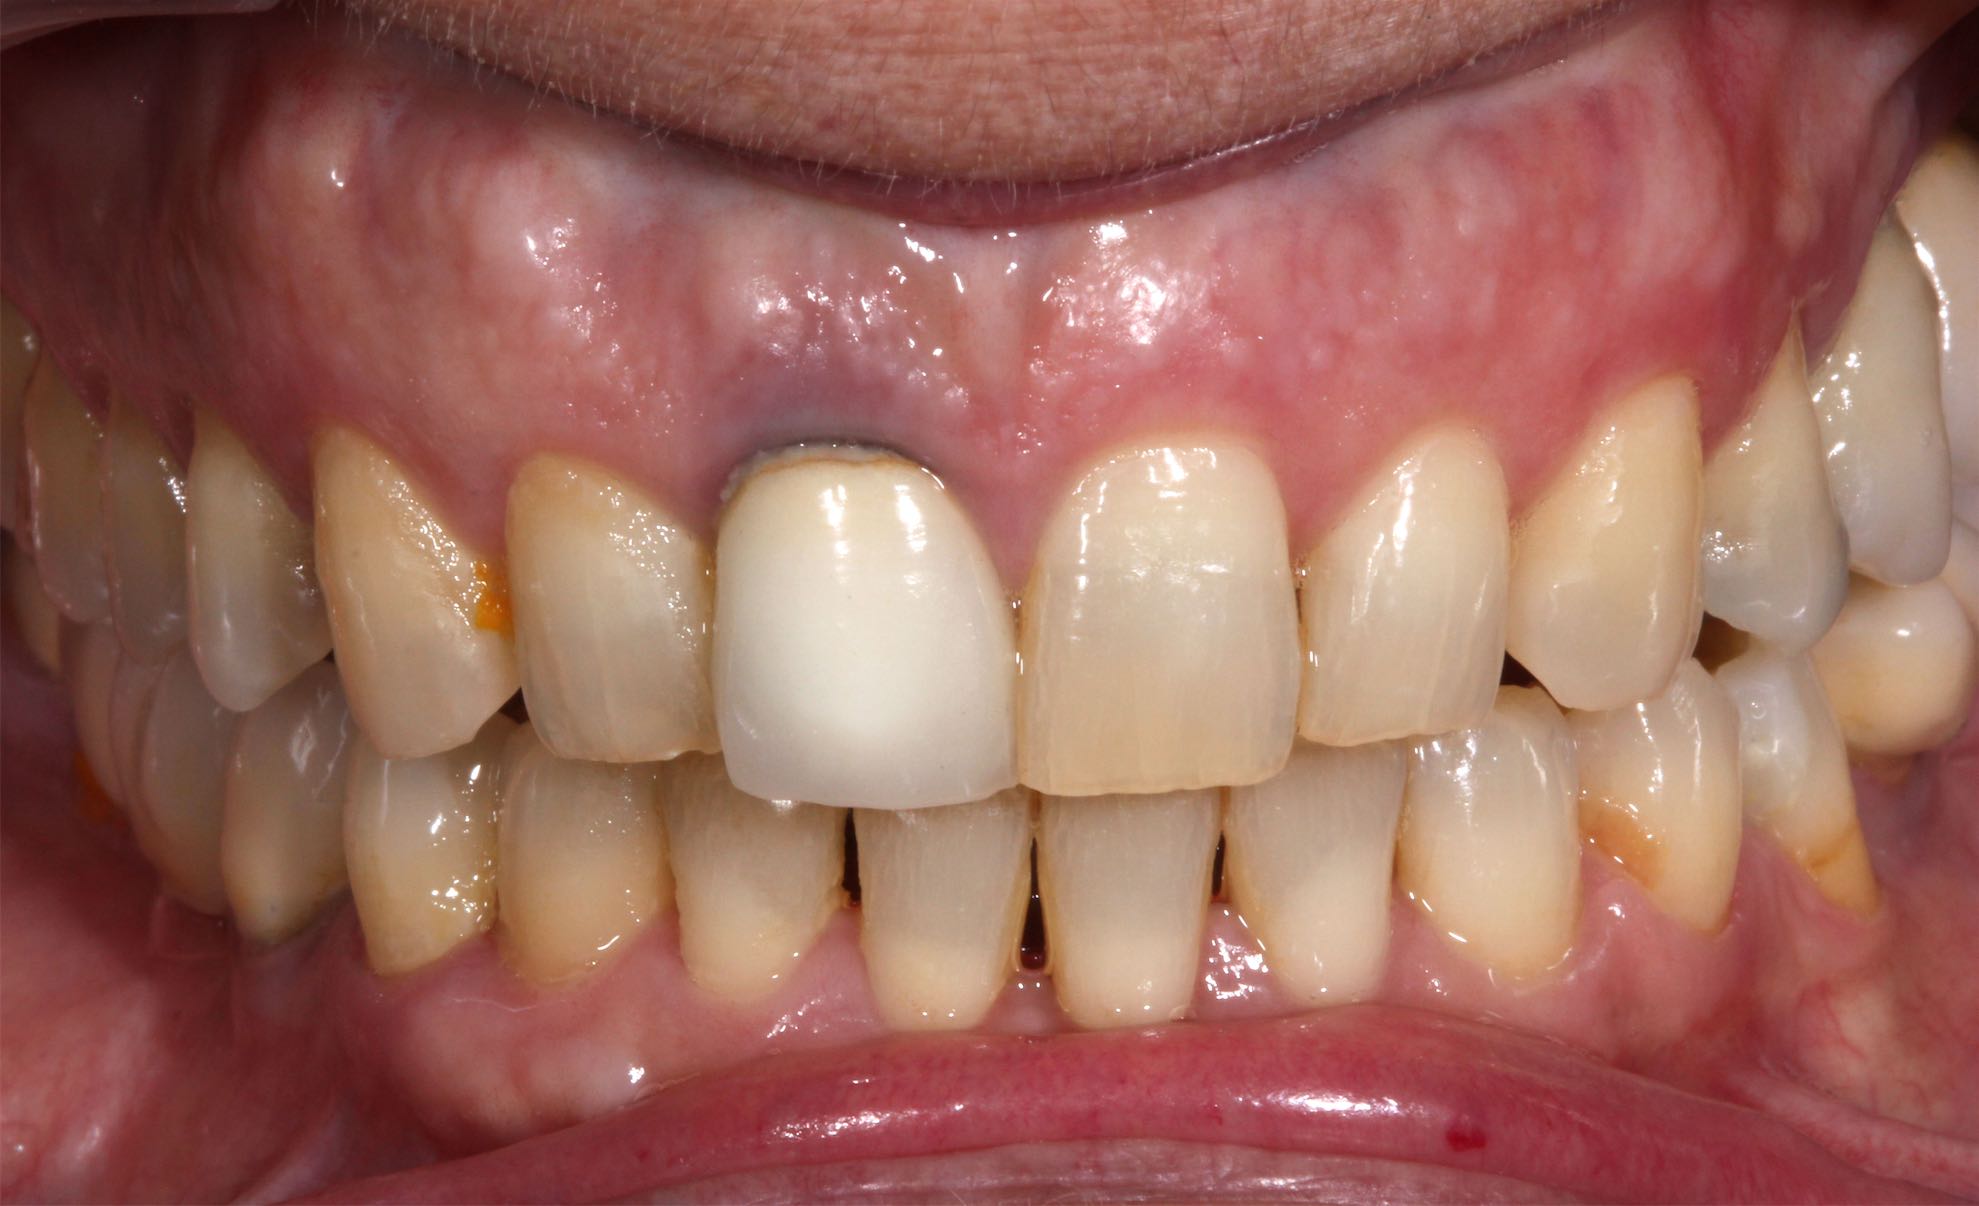

Odontología Estética. Coronas

BeforeAfter